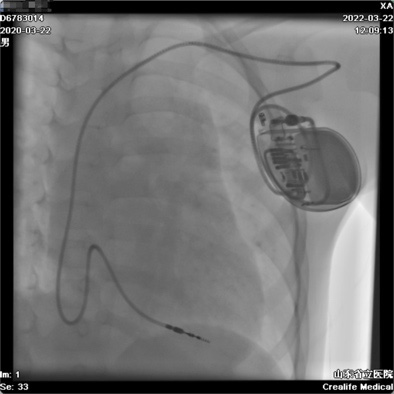

近日,山东第一医科大学附属省立医院(山东省立医院)儿科主任、小儿心脏科主任韩波教授团队成功完成山东首例儿童3.0T磁共振兼容心脏永久起搏器植入手术。

患儿为2岁男孩,宫内即发现心率明显减慢,诊断为先天性Ⅲ度房室传导阻滞,平均心率仅39次/分,入院前1天突发晕厥1次,亟需植入心脏永久起搏器。在院领导及相关部门大力支持下,小儿心脏科全体医务人员进行了病例讨论并为患儿做好了充分的术前准备。3月22日上午8:30,在介入诊疗中心,小儿心脏科主任韩波教授为患儿成功植入了磁共振兼容永久起搏器,测试起搏器各项功能良好,患儿安返病房。